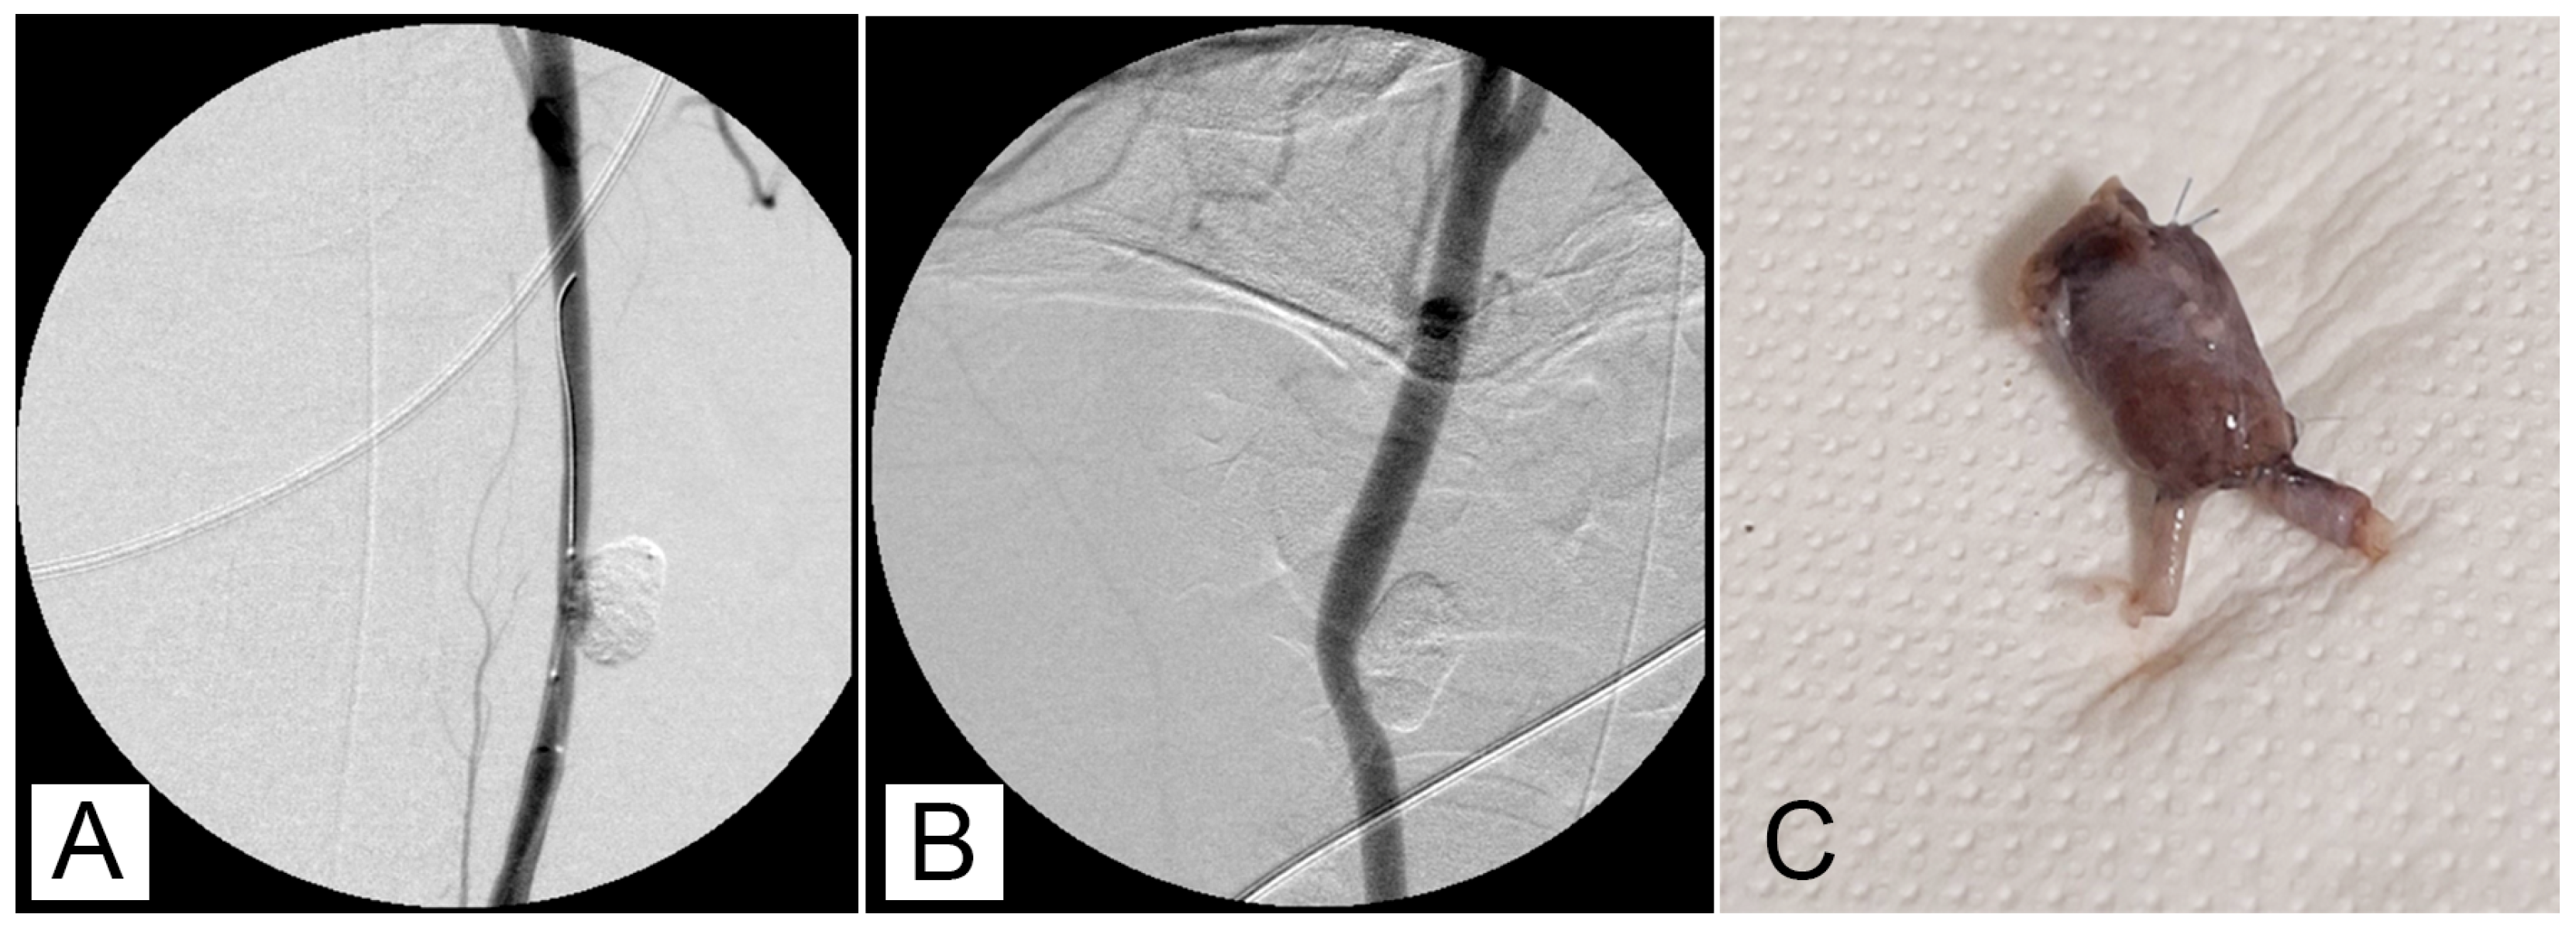

One possible method of cleaning a microcatheter lumen is to flush it with Lipiodol®. Nevertheless, it was occasionally discovered that GEL remained in the hub section of a microcatheter, making guidewire insertion challenging when the microcatheter was reinserted using a guidewire. Another microcatheter was needed in this case. In 15 of the 18 aneurysms, post-packing angiography showed nearly full aneurysm packing (Figure 1).

Figure 1.

(A) Carotid angiography shows the aneurysm before embolization. (B) Attempted embolization using GEL 2:0, 5:1, via a microcatheter inserted into the microaneurysm, with balloon protection (C).

After 30 min of packaging, there was no migration or leakage of GEL. Post-procedure angiographic controls showed a stable occlusion of all the aneurysms with no signs of recurrence (Figure 2A,B).

Figure 2.

(A) An angiographic intraoperative control after embolization with balloon deflated. (B) Follow-up control at 90 days. Occlusion remains stable. (C) Aneurysms excised.